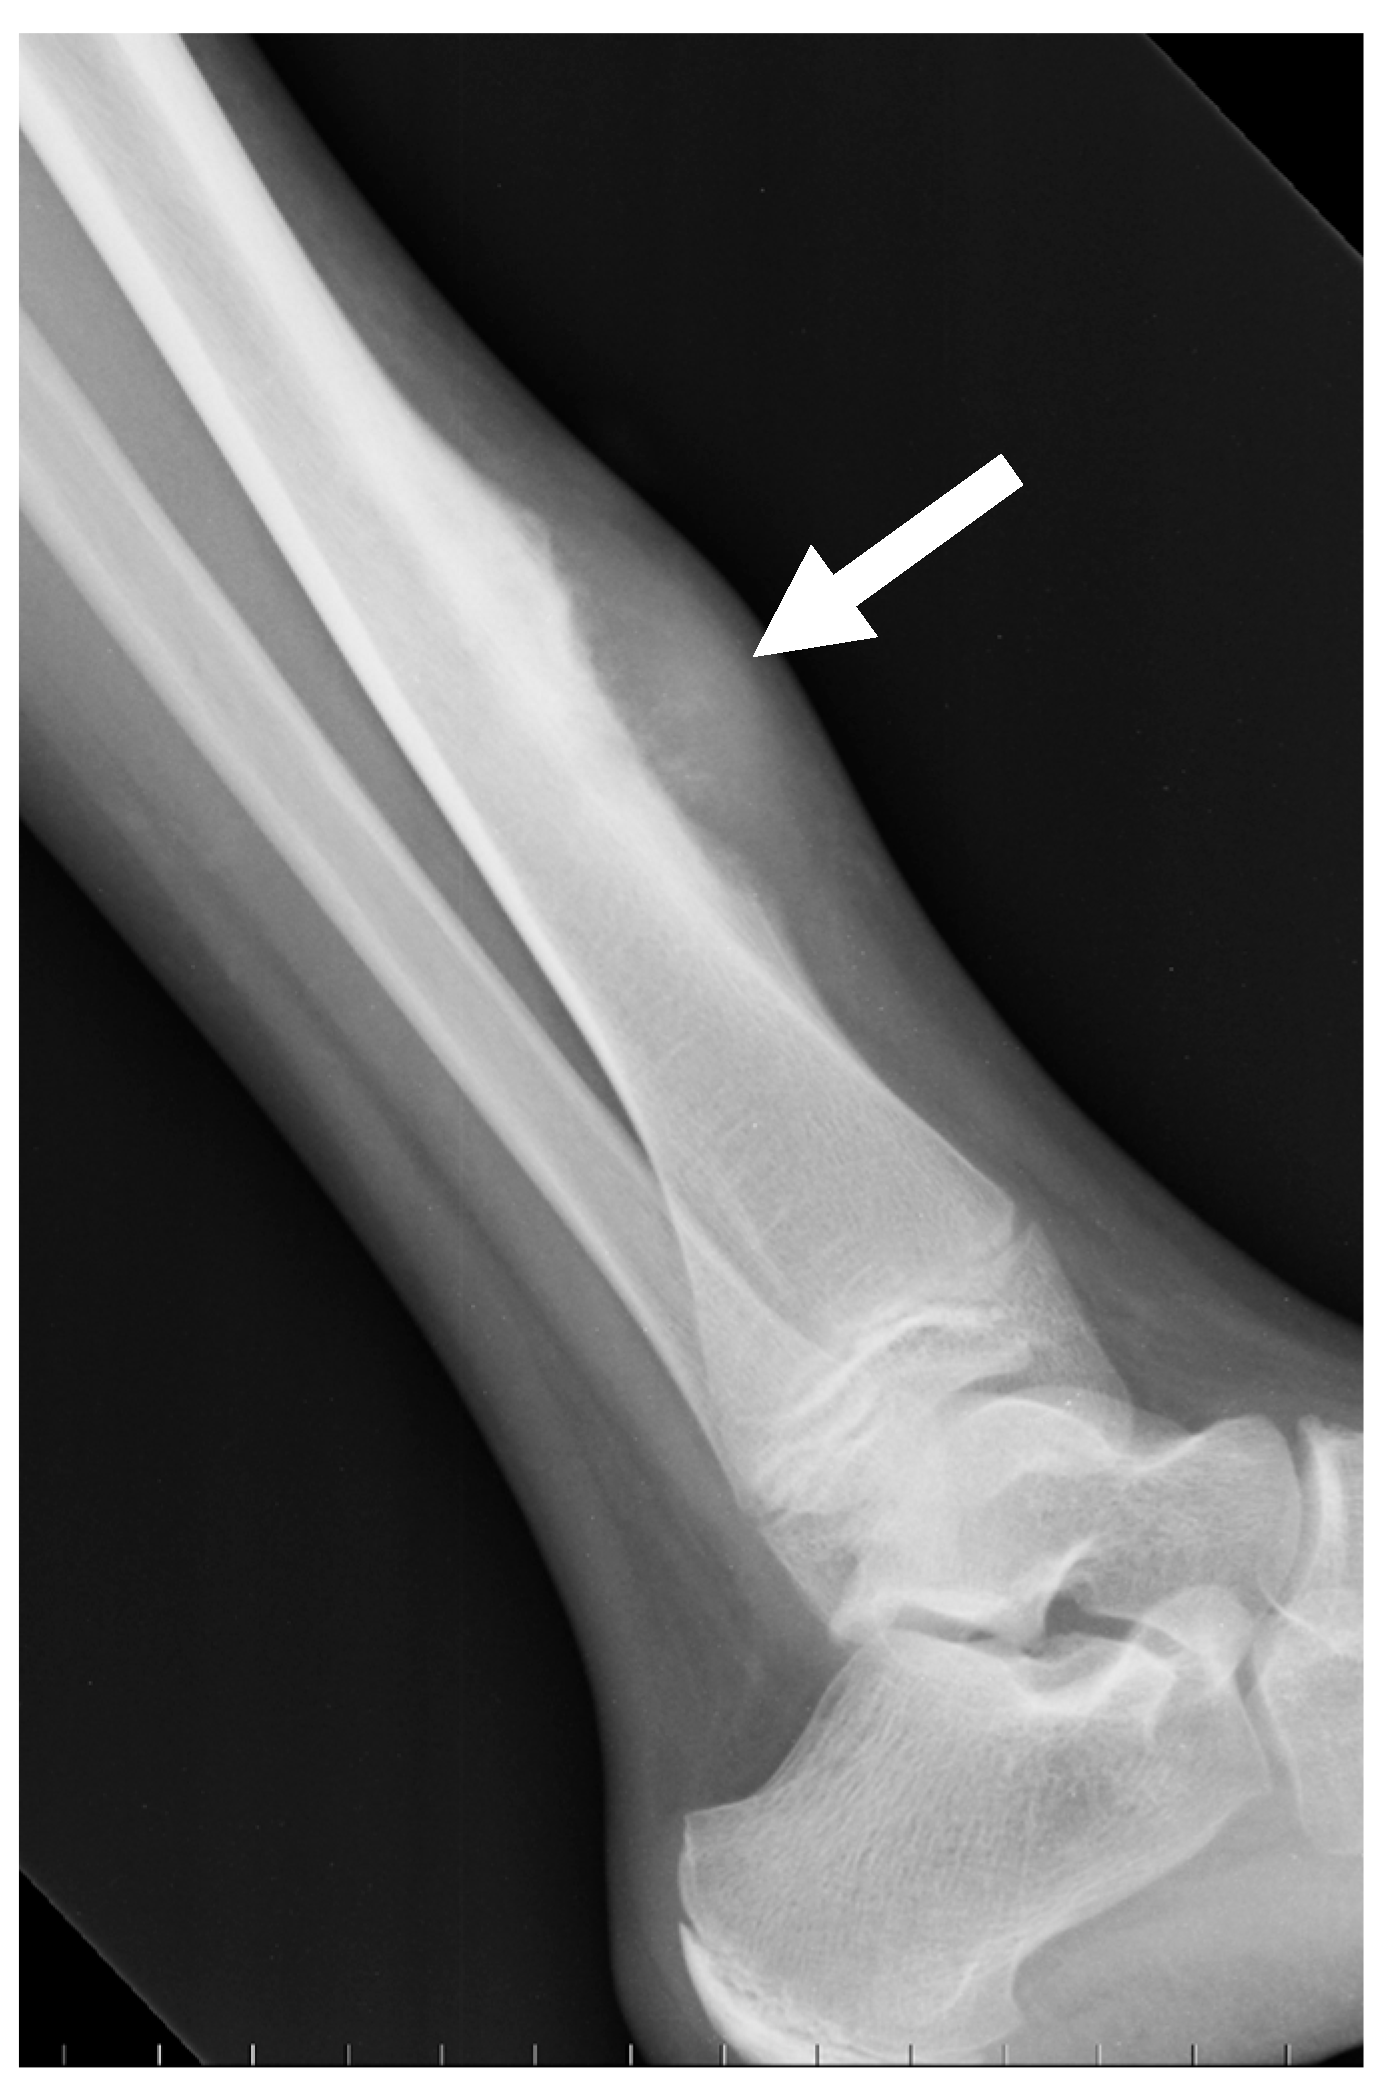

| Periosteal | Periosteal dense mass with well-defined borders | None or sometimes Codman triangle | Cortex may be intact or focally eroded, but bone canal is not involved |

| Periosteal 2 | >1% | 10–20 years old; M:F = 1.5:1 | Tibia and femur (both near knee and in diaphysis) |